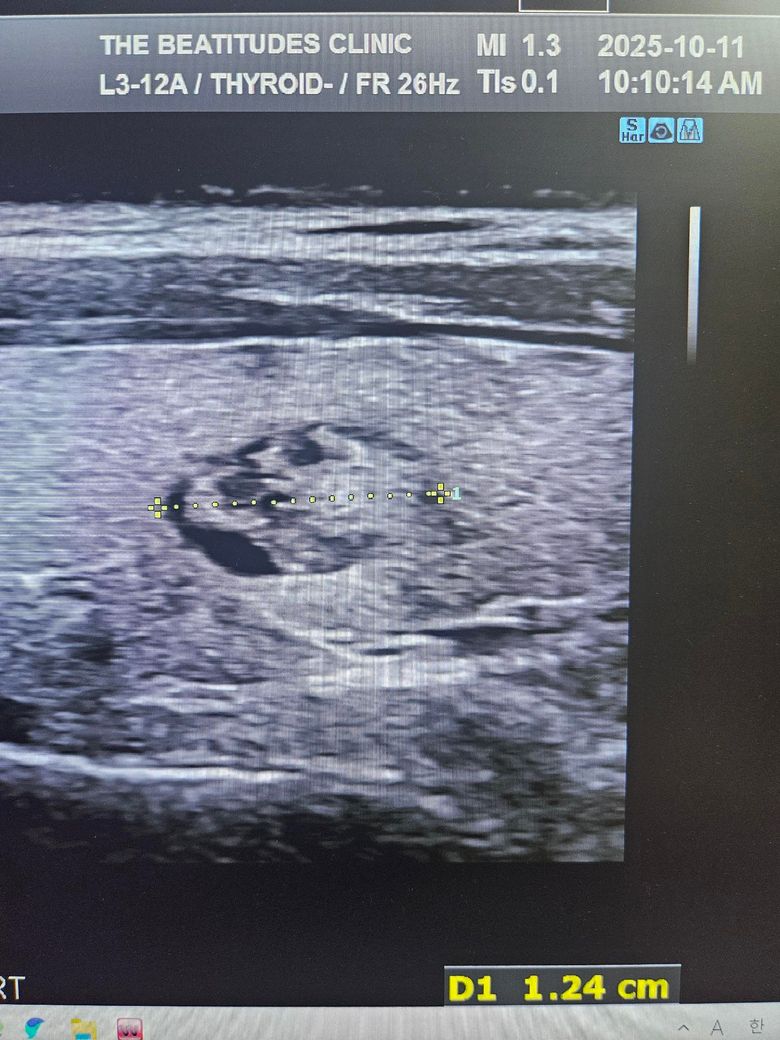

갑상선초음파하고 세침검사 권유받았는데 위의 세개의 사진은 같은 혹이 맞는건가요? 1개 있다고 얘기해줘서 봤는데 사이즈가 이렇게나와서 가로 세로 폭 값인건지 여쭤보고싶습니다

첫번째 사진과 세번째 사진의 경우 같은 결절로 보입니다.

단지 3번째 사진의 경우 크기가 기재되어 있지 않기 때문에

크기만으로 따진다면 이는 애매하다 할 수 있겠습니다.

초음파에서 첫번째, 세번째 사진의 급성 연골 오른쪽에 위치한 오른쪽 갑상선에 동그란 혹이 관찰되며 사진으로는 사이즈를 정확하게 구하기 어렵지만 1.5 cm 이상으로 보이며 혹 안에 균질하지 않은 모습으로 악성 혹은 양성이라고 해도 정기적으로 관찰해야 하는 종양으로 보여 조직 검사를 받는 것은 필요한 것으로 보입니다. 갑상선 종양은 다른 종양에 비해 예후가 좋아 적절한 치료를 받으면 대부분 완치가 가능합니다